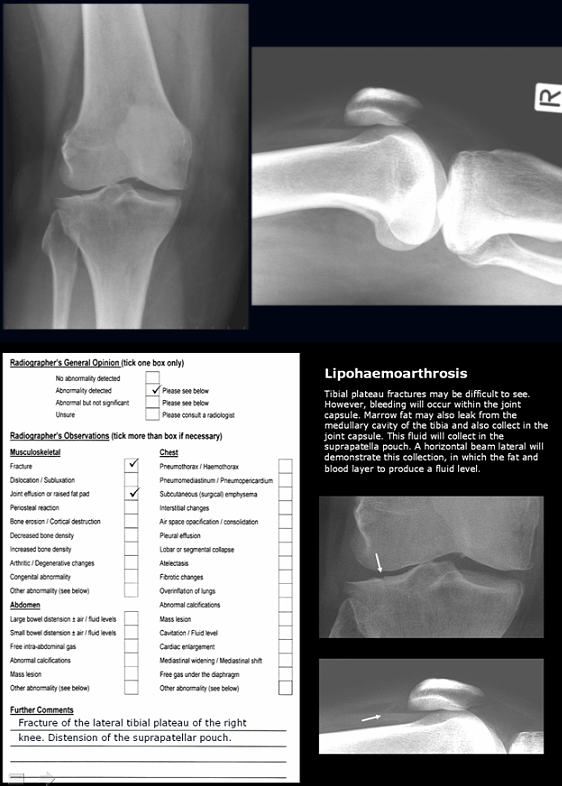

- self-guided Microsoft PowerPoint presentations emailed to each participant approximately every 2 weeks. Presentations included directed-learning material and self-test case studies with model answers (Fig1)

Figure 1: An example of the Microsoft PowerPoint directed learning, self-test image interpretation quizzes (top) with model answers using the radiographer opinion form (ROF) format.